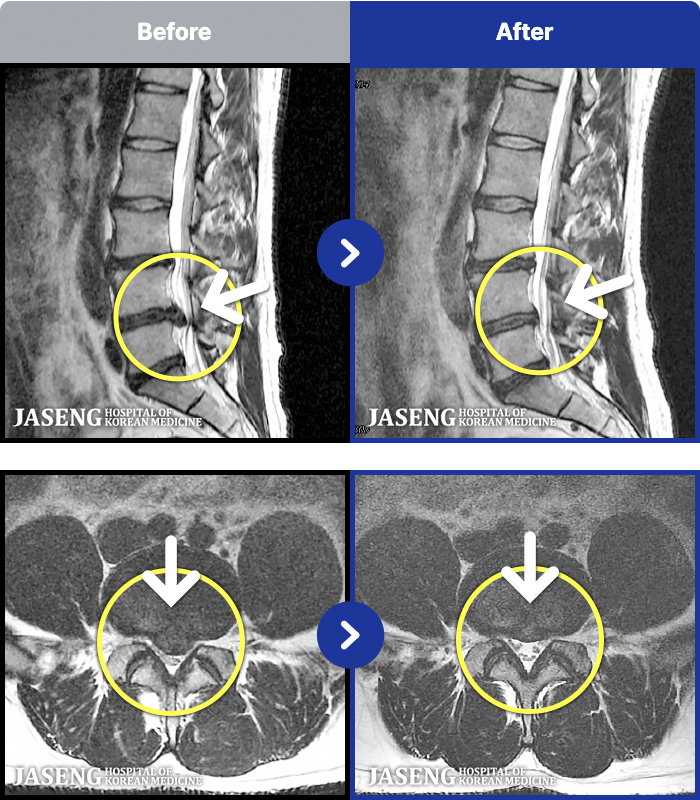

88 MRI ũ ʸ Ȯϼ.